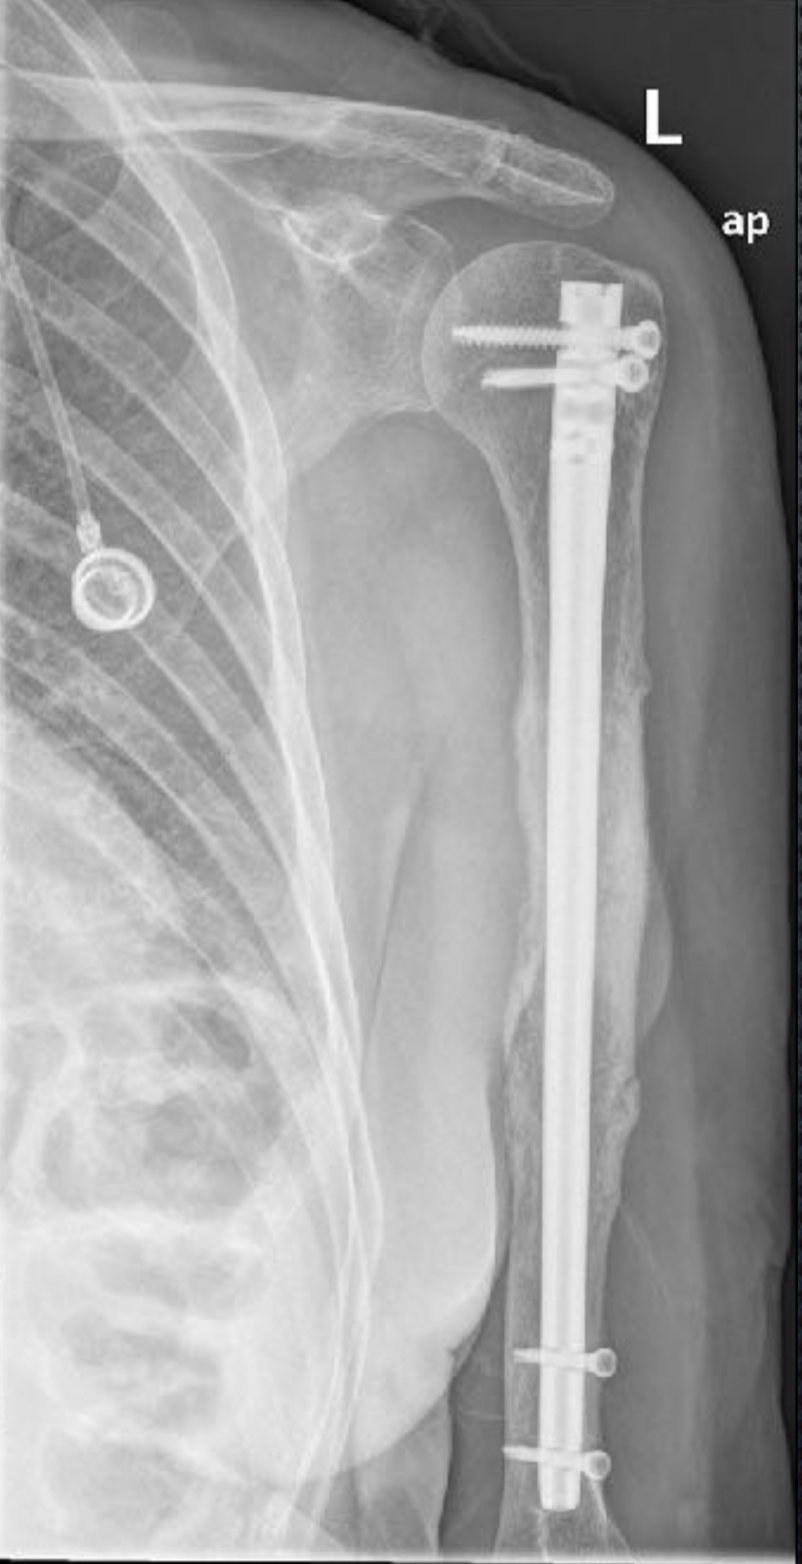

👉 Ejemplo: una fractura en el húmero que impide mover el brazo.

Fractura patológica de humero

Osteosíntesis con clavo humeral de fractura patológica